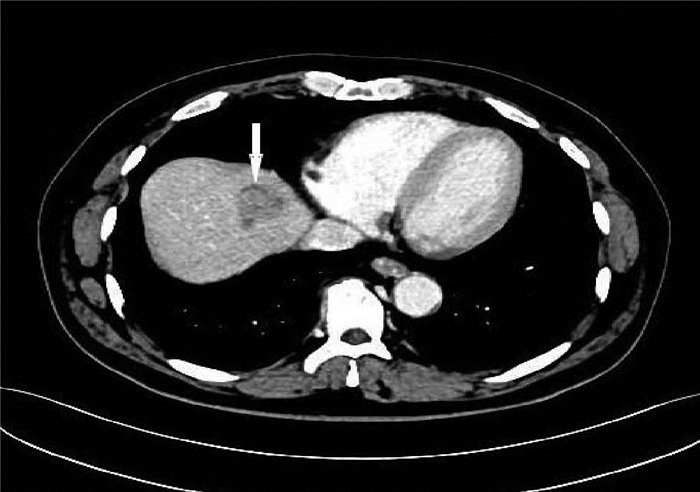

Primary liver cancer with prostate metastasis: A case report